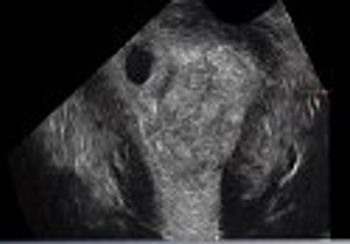

This case report features an underappreciated clinical entity-angular pregnancy. What do you know about this rare obstetric complication?